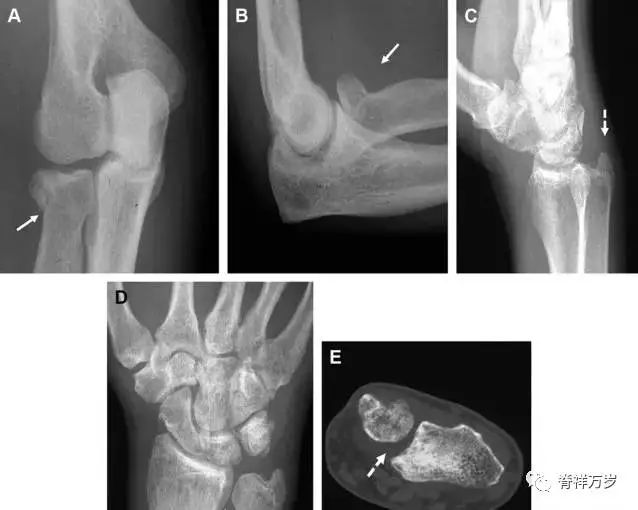

多发生于摔倒时,手掌撑地,受到轴向、外翻应力所致。常规的前后位片容易漏诊,常需加拍内斜位、外斜位、桡骨头-肱骨小头位片。后脂肪垫可见(位于鹰嘴窝内,一般不可见)和/或前脂肪垫抬高常提示骨性损伤。

图 2 桡骨头骨折。前后位(A)和侧位(B)片示后脂肪垫抬高(黑色箭头),前脂肪垫抬高(白色箭头),呈「帆船征」,其它表现正常;外斜位(C)和桡骨头–肱骨小头位(D)示桡骨头关节内骨折线(虚线黑箭头)累及桡骨颈(虚线白箭头)。